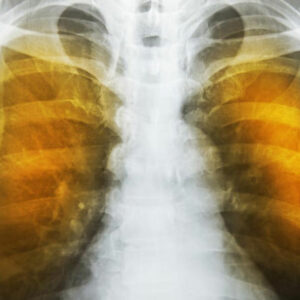

What is emphysema and what are its complications?

Emphysema is an oppressive respiratory disorder which results from the disintegration of the alveoli, i.e., the tissues where the interchange of gas with blood takes place. Destruction in any large scale will reduce the gas transfer area and the process of gas transfer itself, leading to oxygen starvation or hypoxia.